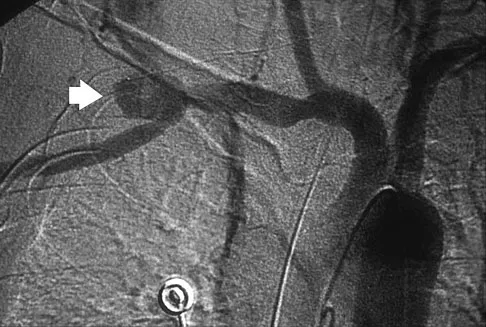

Question 77

A previously healthy 65-year-old woman has a closed fracture of the right clavicle after falling down the basement stairs. Examination reveals good capillary refill in the digits of her right hand. Radial and ulnar pulses are 1+ at the right wrist compared with 2+ on the opposite side. In the arteriogram shown in Figure 36, the arrow is pointing at which of the following arteries?

Explanation